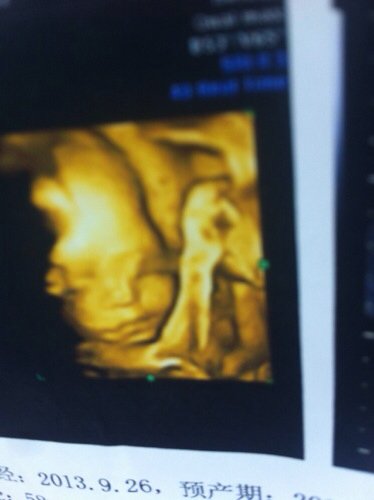

这两张四维彩超图有什么问题吗?是不是眼睛和鼻子怪怪的,帮忙看下谢谢了 点击展开 匿名用户 2014-04-09 15:18 为您推荐: 其他回答 病情分析: 你好,这张图片面部发育良好。 指导意见: 宝宝小时候的面部发育都是看起来怪怪的,你的宝宝B超没有异常。以前你应该学过哺乳动物发育过程都这样。 匿名用户 2014-04-09 15:31 相关问题 帮忙看下这张四维彩超照片鼻子和眼睛是不是有问题? 七个月的宝宝鼻子上眼睛上怎么像张斑是的 昨天打流脑,昨晚眼睛眼屎多的眼睛挣不开,手很热,嘴巴张着出气鼻子还不通气,不知道是感冒还是打流脑引